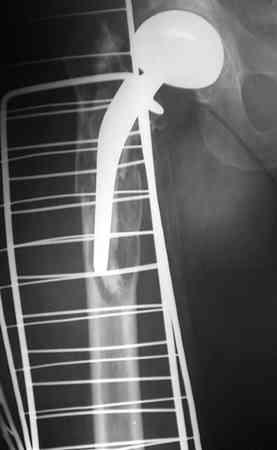

Анамнез: Болеет с 1995 года. В 2000 и 2001 годах произведено тотальное эндопротезирование обоих тазобедренных суставов (сначала левого затем правого). Сейчас в области левого бедра в в/3 имеется резкий отек, боль, крепитация. Диагноз:Состояние после тотального эндопротезирования обеих Т\Б суставов, перелом в/3 левого бедра. Нога уложена на шину Беллера с дисциплинирующим вытяжением. Тактика оперативного лечения? Заранее благодарю! С уважением, А.В.Владзимирский Донецкий НИИ травматологии и ортопедии

Привет Антон. Дальний Восток советует (правда ранее мы все учились в Украине - Харьков и Киев - мои школы ортопедии). Конкретика. Имеется

перипротезный перелом на фоне нестабильной ножки протеза. Для прогнозирования приличного результата у данного бедолаги я бы предложил -1.

Ревизию бедренного компонента 100%, замену ножки на длинную, скажем Вагнера или другую -модульную с дистальной фиксацией и обязательно! с костной

пластикой проксимального дефекта бедра чипсами или стружкой, но своими имеется дефект 2-3 типа по W. Paproski) + перелом. Ждать милости от времени

В очередной раз вызывает удивление установка биполяра у молодого пациента, но дело не в этом. Имеется перелом с нестабильностью бедренного цементного компонента. Значительный дефект костной ткани проксимального отдела бедра.

Следует убрать ножку и остатки цемента, заменить на Вагнеровскую ножку (в крайнем случае на длинную цементную), добавить костную пластику проксимального отдела. Тазовый компонент заодно заменить на бесцементный.

Уважаемый Антон,

По Ванкуверовской классификации это 2А тип перипротезного перелома на фоне нестабильности ножки эндопротеза и остеолиза проксимального отдела бедра. Решение - удаление предыдущей ножки, имплантация ножки дистальной фиксации. Канал виден на ограниченном участке, исходя из увиденного, я бы предпочел цилиндрическую ножку 200 мм полнопокрытую. Фрагменты собрал бы вокруг ножки серкляжами. Если будут мелкие фрагменты, то есть смысл взять кортикальные аллографты и поджать фрагменты по типу вязанки хвороста. Отношение к чипсам двоякое - на любителя, главное - надежная дистальная фиксация ножки, обеспечивающая первичную стабильность. Что-то похожее мы оперировали несколько лет назад, качество первичных Р-грамм оставляет желать лучшего, но суть понятна. Результаты через 3 года.